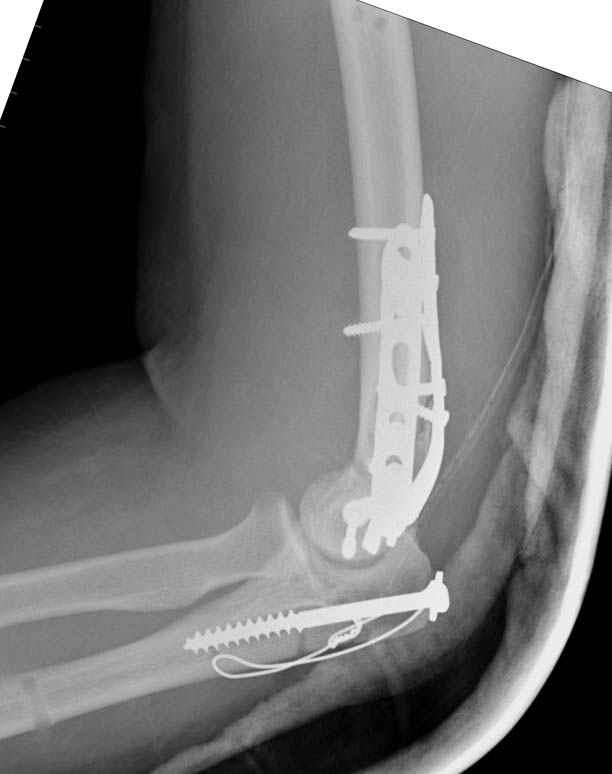

Примерный случай, только перелом был открытый, в задне-медиальной стороне рана около 2 см по характеру "изнутри кнаружи", неврологический статус со слабостью сгибания мизинца, также слабая абдукция и аддукция указательного пальца и сгибания в кисти.

Больному сделали обработку и наложили временный аппарат внешной фиксации плечо-предплечье.

На шестой день сделали открытую репозицию чрезлоктевым доступом двумя locking plate, локтевой нерв был ушибленным, после операции положительная динамика в Flexor Carpi Ulnaris. Фиксацию локтевого отростка произвели tension band technique с дополнительным шурупом.

Этапы операции на снимках....

Джолдас Кульджанов